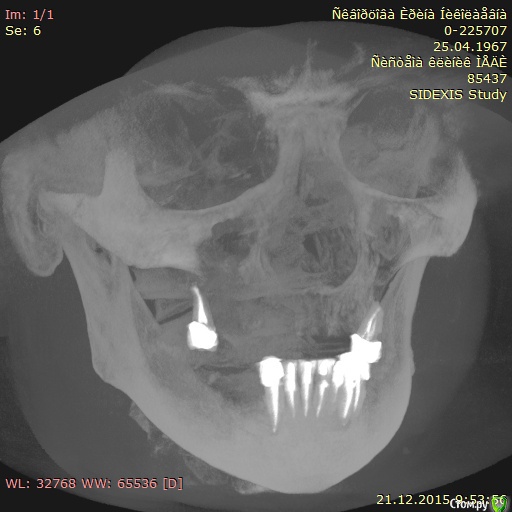

Tushka Опубликовано 4 января, 2016 Поделиться Опубликовано 4 января, 2016 Здравствуйте. Пациент женщина 49 лет, есть серьезные проблемы.Сейчас съемные протезы на обе челюсти. На верхней челюсти нет костной ткани. На нижней челюсти 1мм костной ткани.Хотим сделать несъемные протезы, на обе челюсти. Есть снимки DICOM, архив ZIP можно загрузить из Google Drive по ссылкеhttps://drive.google.com/file/d/0B8QE61hrloGVYTBsTW9hUzd0ejA/view?usp=sharing Пока все врачи рекомендуют скуловые имплатны - зигому Есть ли еще варианты решения проблемы? Заранее благодарю за ответ. Ссылка на комментарий

Tushka Опубликовано 5 января, 2016 Автор Поделиться Опубликовано 5 января, 2016 (изменено) Снимки прикрепил во вложении.Экспортировал их из КТ, ссылку на которую давал, с помощью бесплатной программы RadiAnt DicomНа всякий случай эти два снимка и еще 512 экспортировал в стандартный формат jpeg и выложил в общий доступ по ссылке https://drive.google.com/file/d/0B8QE61hrloGVaHJTczBiMjlNSGM/view?usp=sharingСпасибо! Изменено 5 января, 2016 пользователем Tushka Ссылка на комментарий

Evikrol Опубликовано 5 января, 2016 Поделиться Опубликовано 5 января, 2016 Вы не совсем то выложили, но наверху кажется можно all on 4 Ссылка на комментарий

IvanK Опубликовано 6 января, 2016 Поделиться Опубликовано 6 января, 2016 Можно обойтись и без скуловых, но с наращиванием кости 1 Ссылка на комментарий